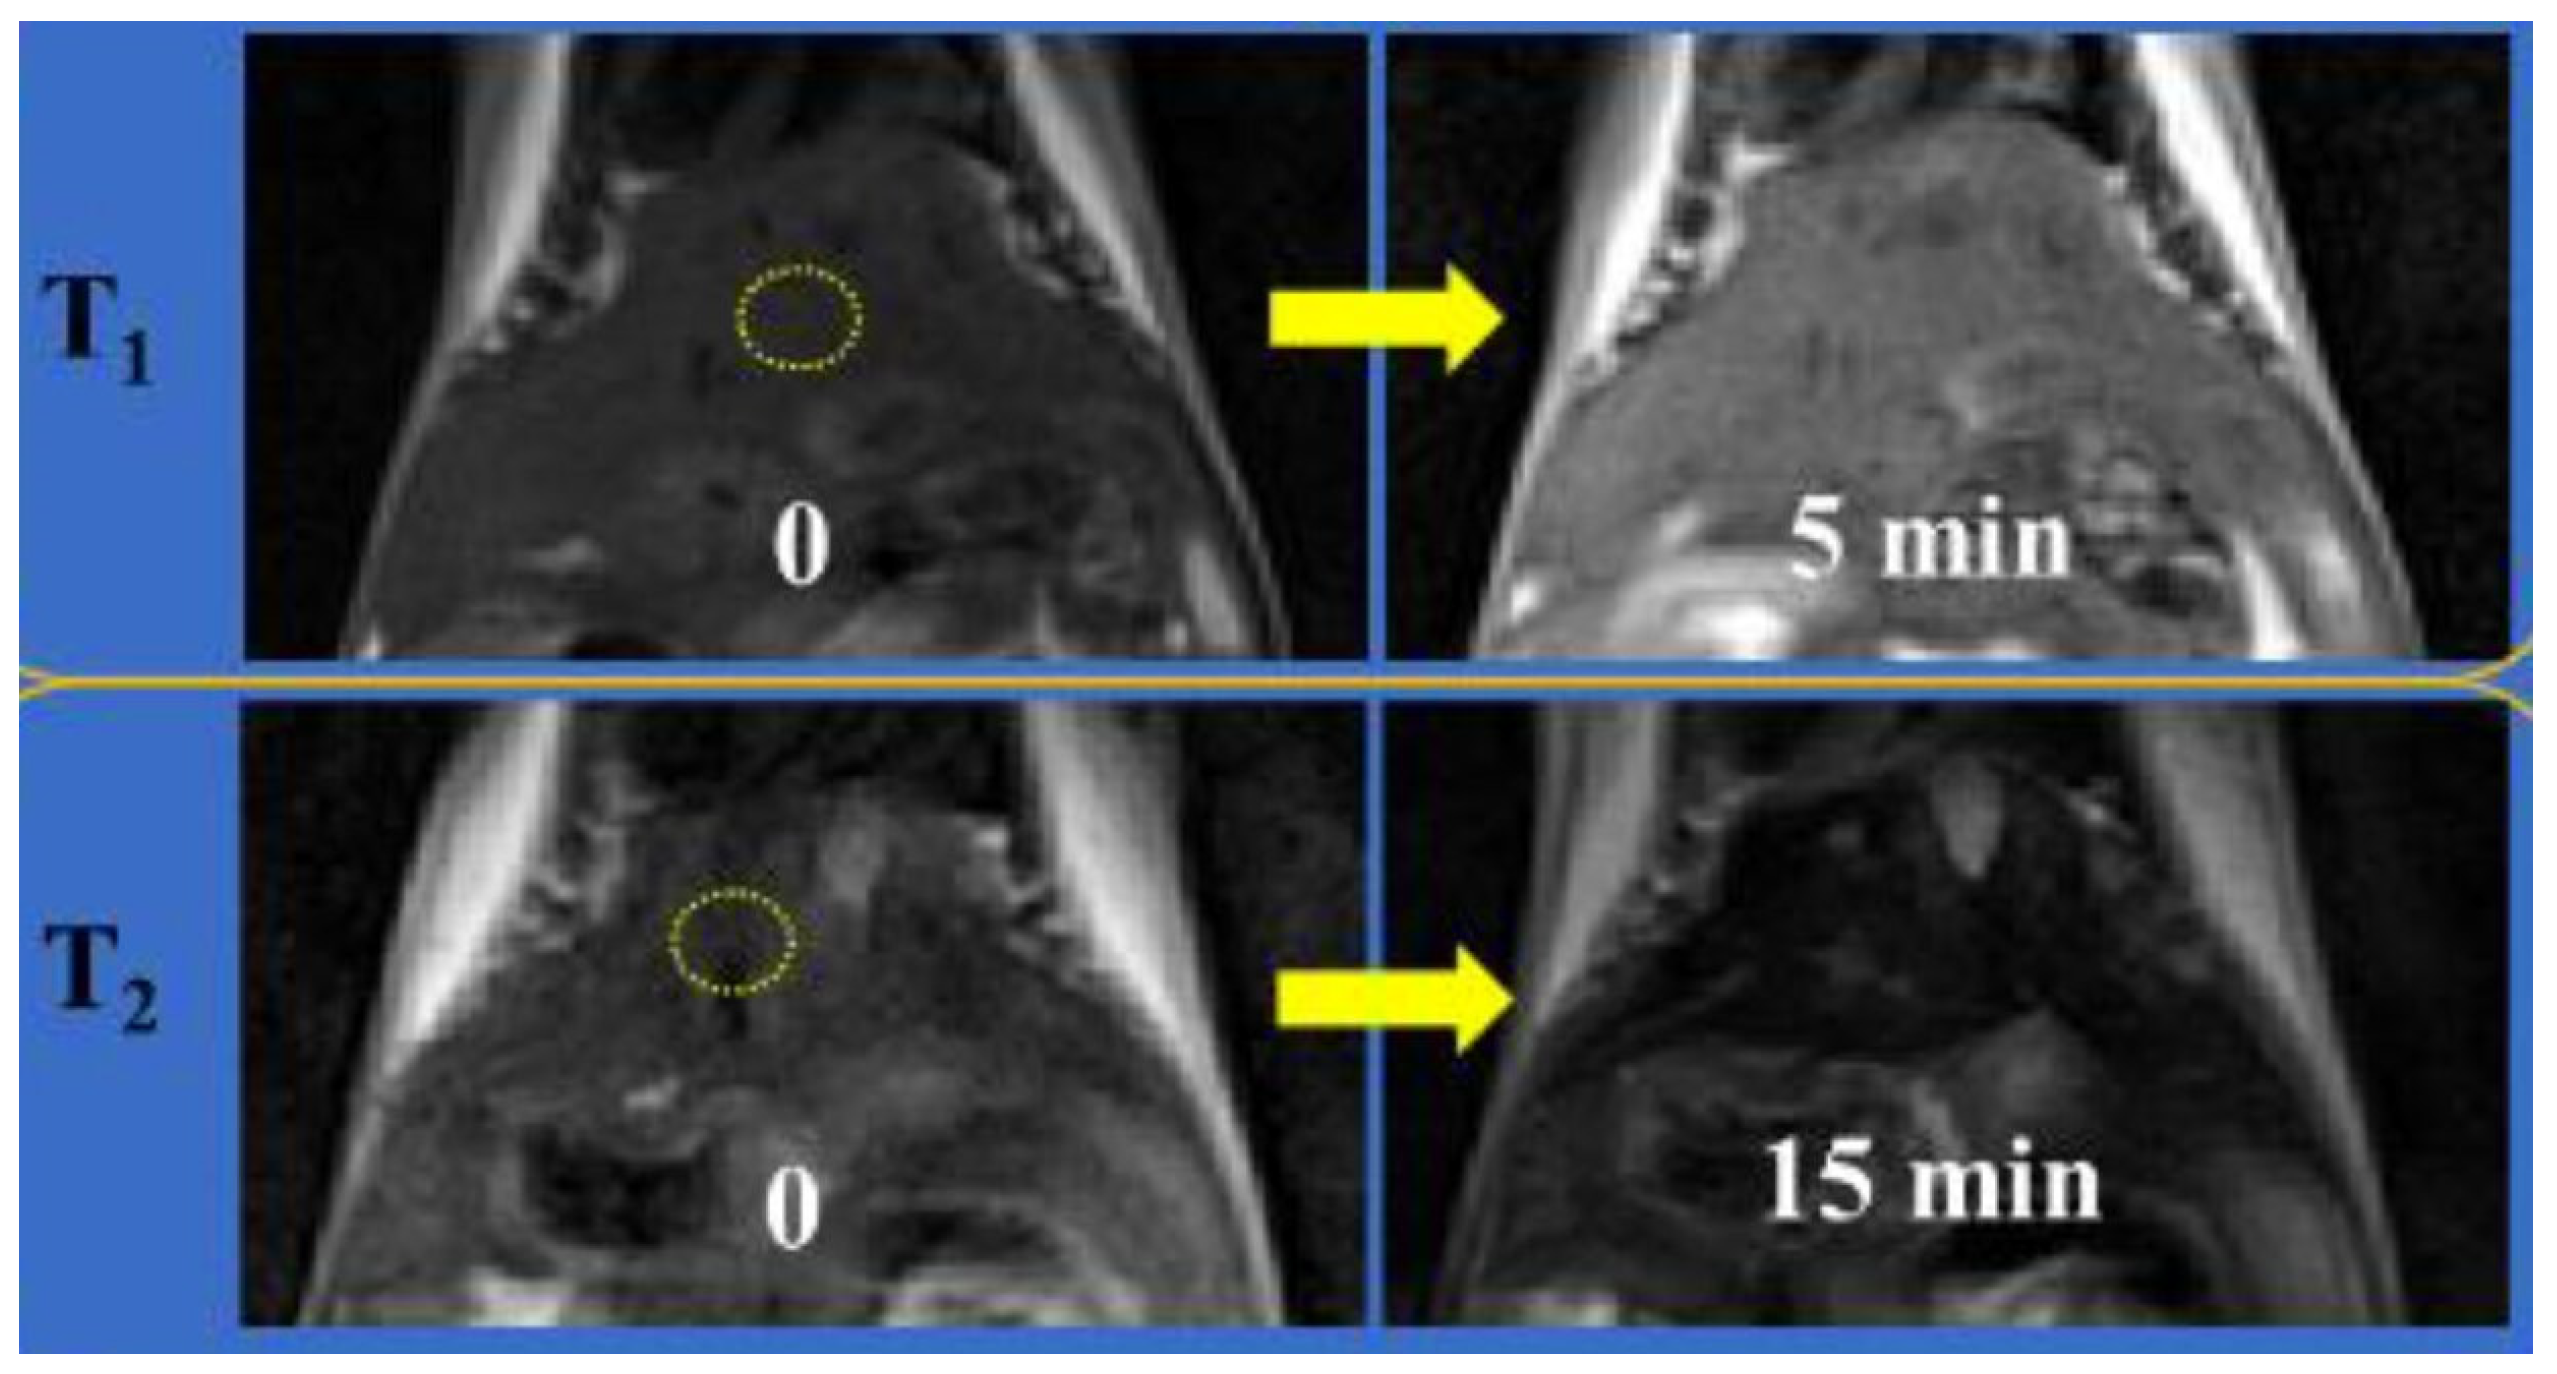

| IONA → ESIONP dispersed pH 7.4 → 5.5. | 3.2 → 108.0 | 5.1 → 22.3 | 34.2 → 4.1 | 3.0 | 80 | In vitro A549 cells In vivo tumor mice | [92] |